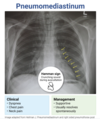

This CXR and scenario of a women who did not finish abx due to recent PNA. What dx?

empyema